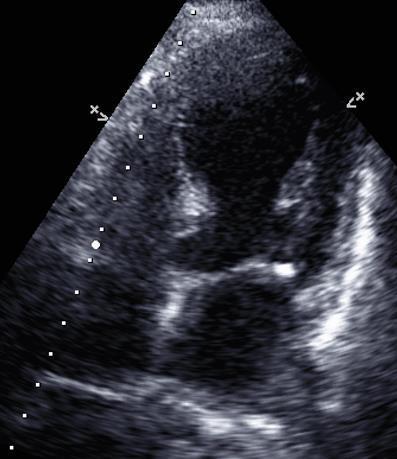

LARYNGEAL SYNOVIAL SARCOMA THAT METASTASIZED TO THE HEART

Christopher N. Matthews1 , Syed Farrukh Mustafa1 , Sidra Salman1 , Akshaya

Gopalakrishnan1, James Salonia1 , Deepika Misra1

1Mount Sinai Morningside-West Hospitals, Icahn School of Medicine at Mount Sinai, New York, NY, United States

Presented at the American College of Cardiology (ACC) Annual Meeting that was held in New Orleans, Louisiana, United States from March 4-6, 2023.